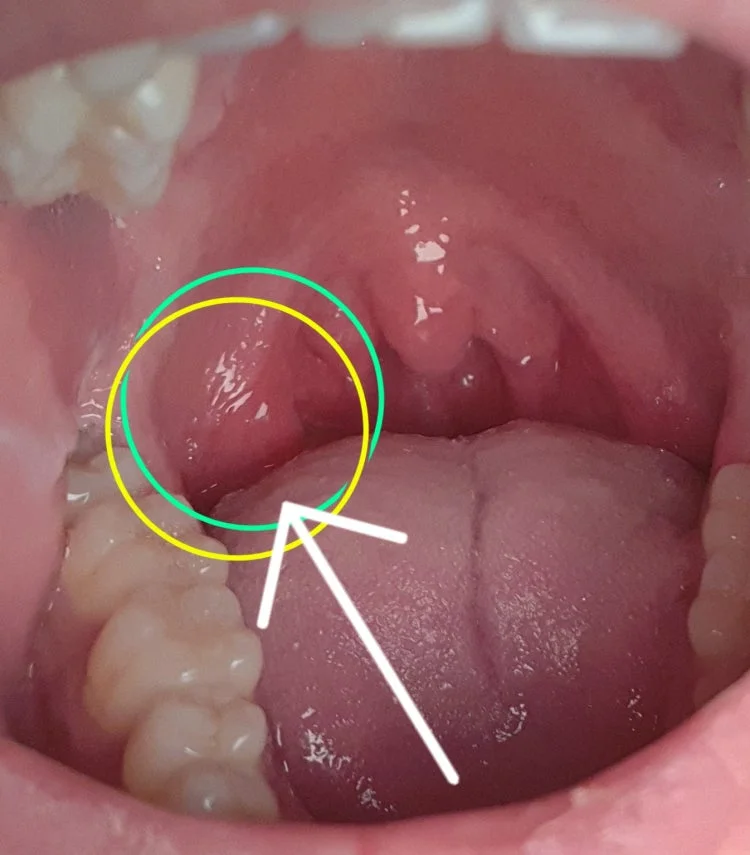

희안하게 동그라미친부분이 부었더라구요

* 부은 위치: 이미지에서 동그라미 친 부분 (정확한 위치는 사진상으로 특정하기 어렵습니다.)